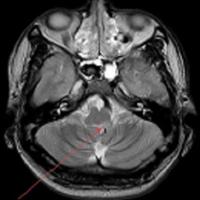

尽管患者CT表现正常,但根据患者的症状和体征,怀疑该患者患有延髓外侧综合征。对患者进行脑MRI检查,证实左侧背外侧髓质梗死(图3)。

图3